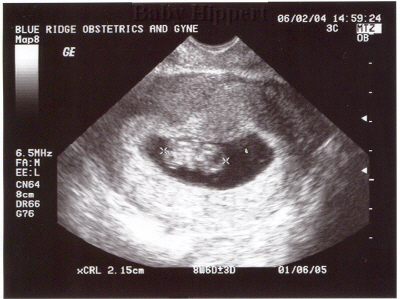

Ultrasound

Taken On June 2nd 2004   Taken On September 24th 2004   Taken On October26th 2004